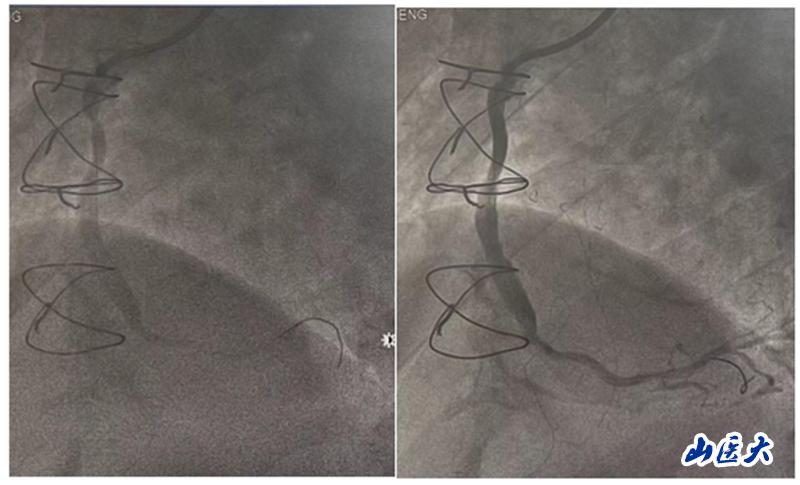

在手术中,团队发现患者的前降支、回旋支口部和右冠脉近段均存在闭塞情况,升主动脉-右冠脉桥血管近端狭窄约90%。团队决定对升主动脉-右冠脉桥血管进行介入治疗。他们快速准确地判断了病变血管的范围,并选择了激光消蚀辅助以及合适的球囊和支架进行干预治疗。手术后,患者安返病房,未再出现胸闷及气紧等不适症状。

准分子激光冠脉消蚀技术主要通过光化学效应、光热效应和光机械效应三种原理达到治疗效果。它发出高能量脉冲,引起细胞的碳键断裂,释放的能量使细胞内水温升高,导致组织汽化并产生压力。通过组织的迅速膨胀和收缩,可以达到消蚀斑块物质、改善冠脉血流的效果。这一技术通过消蚀病变血管内斑块,达到改善冠脉血流的效果,特别适用于处理复杂性日益增加的冠状动脉介入手术。